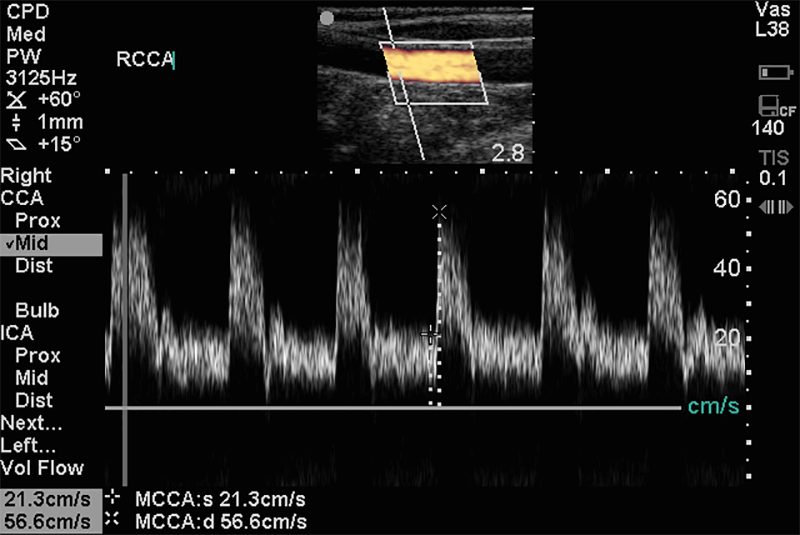

Doppleres érvizsgálatok az erek tágassága, faluk állapota, lefutása mellett, színes és pulzus dopplerrel vizsgálható bennük a keringés iránya, mérhető a keringés sebessége.

A kóros tágulatok és szûkületek, thrombusok, az erek részleges vagy teljes elzáródása kimutatható, mérhető. Érvizsgálataink a nyaki (carotis) erek állapotának tisztázására vonatkoznak.

Az érelmeszesedés korai stádiumban való felismerése a súlyos szövődmények megelőzése érdekében rendkívüli fontossággal bír. A már kialakult érbetegségekben az ultrahang a terápia megválasztásához feltétlenül szükséges.